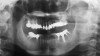

Fig 7. Panoramic x-ray before treatment.

Figure 7

From radiographic examination, tooth No. 18 was found to have a poor prognosis due to furcation bone loss. The cephalometric x-ray showed a skeletal class II relationship, a reduced mandibular plane angle, flared upper incisors, a deep bite, and significant overjet (Figure 6). The panoramic radiograph confirmed many restorations and that No. 19 was a dental implant (Figure 7). There were no symptoms of temporomandibular joint disorder.